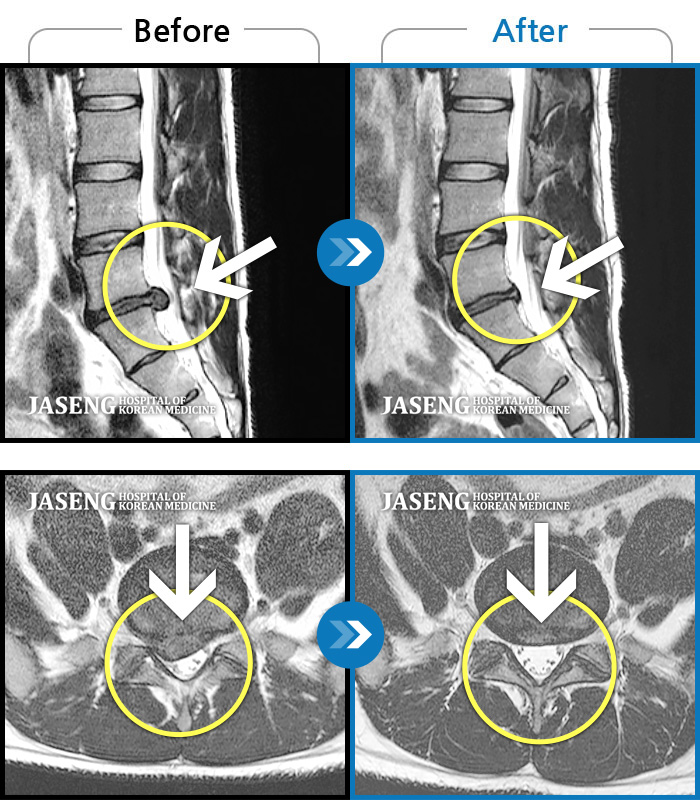

MRI 치료사례

허리와 다리에 찌르는 듯한 통증